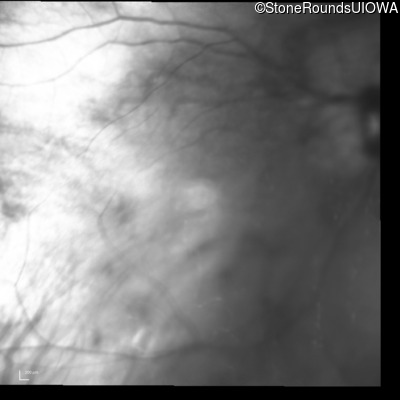

Infrared Fundus Photograph - Left - 20/30 +1

Exemplar